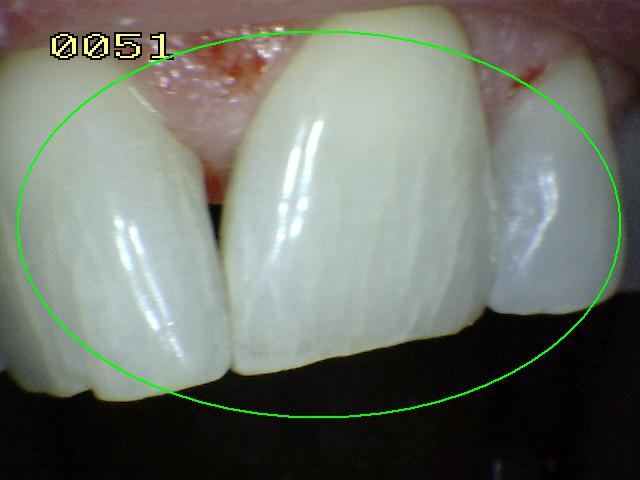

Código 2

(Caries Inicial): Lesión de

caries observada en esmalte en estado húmedo y permanece después de secar

- Cuando la superficie de esmalte se

observa en estado húmedo hay un cambio de color

(mancha blanca o marrón) y después del secado con aire

por 5 segundos se visualiza los rasgos típicos

de la (mancha blanca

/ marrón). Estas lesiones se encuentran tocando el

margen gingival o a un milímetro de este.